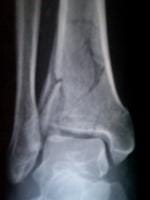

Definitivamente es una fractura difícil, no puedo ver bien en las imágenes que son muy pequeñas, pero parece verse un trazo articular. ¿O hay varios?

Gracias por la respuesta yo vivo en guerrero arcelia, caí de una altura de un metro poco menos, no dolió, no duele puedo mover dedos, y n siento ningún dolor calambre ya tengo dos meses de caído pero 15 días traía una férula, la verdad no hay muchos especialestas por acá, en chilpancingo uno digo operación, pero otro dijo yeso y pues, me pusieron hace casi 8 semanas bota de fibra de vidrio yo me siento bien no apoyo el pie sentado lo pongo en el piso y no me molesta pero la verdad, no se que tan mal esta o que pronostico tenga no puedo trabajar, pues es la pierna derecha y pues no se realmente para cuando me podre mover, manejar etc gracias

De verse bien, se ve.

Tal vez en un inicio yo habría optado por la cirugía, pero ahora se ve bastante bien.

¿Creoq eu el tiempo que llevas es buen tiempo y no de ven desplazados ls fragmentos

No veo mayor problema eh!

Creo que estas bien